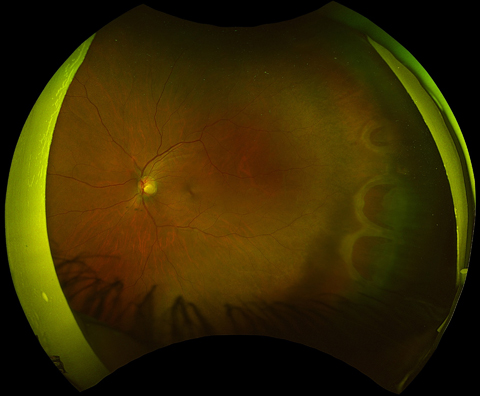

Horseshoe tears in the retina after traumatic posterior vitreous detachment